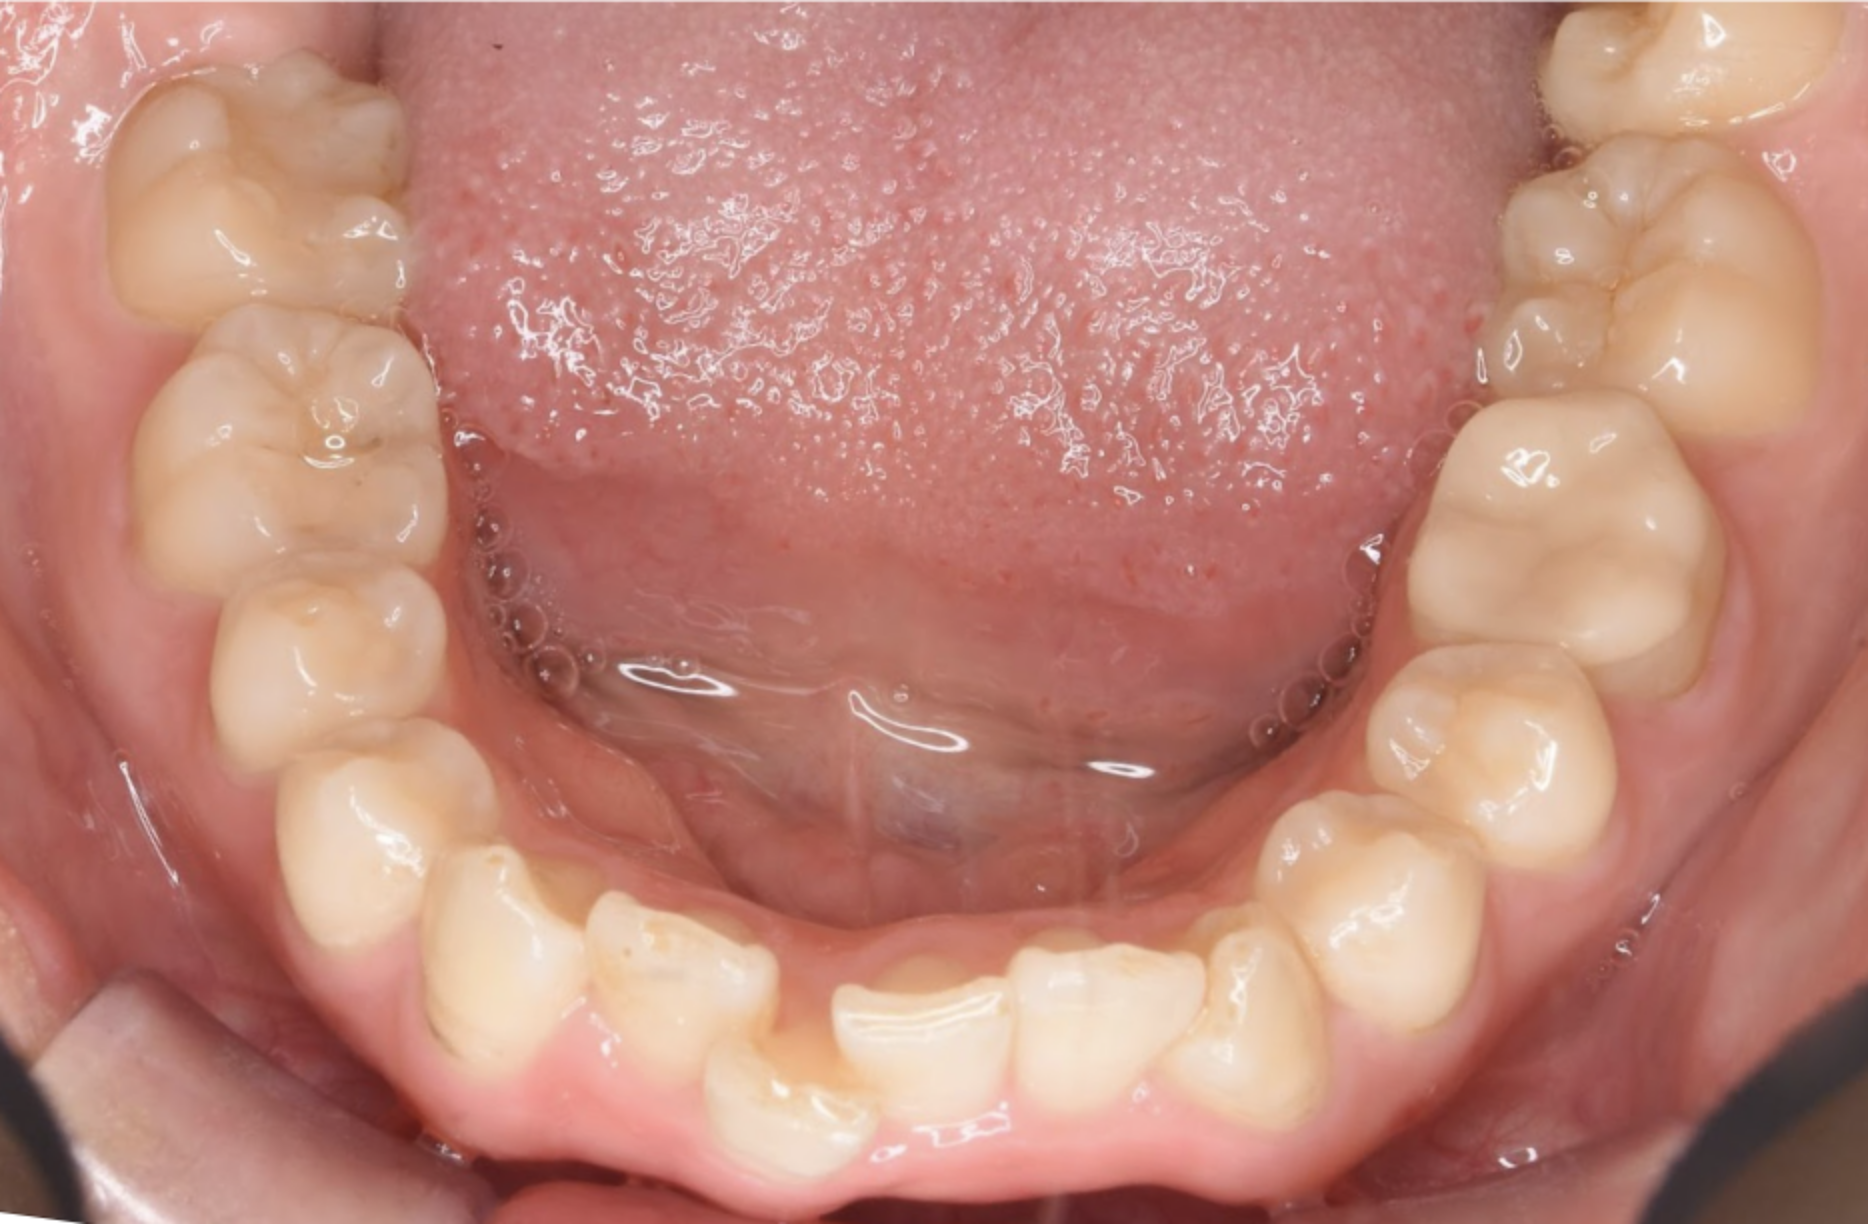

治療後の口腔写真

Before